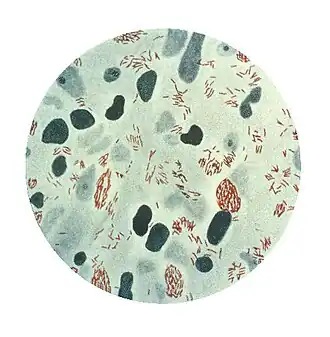

| leprabacterie in Ziehl-Nielsen-kleuring | |||||||||||||

Mycobacterium leprae of bacil van Hansen is genoemd naar de Noorse arts Armauer Hansen die hem in 1873 ontdekte. Deze ziekteverwekker valt onder de Mycobacterium genus en veroorzaakt de ziekte lepra.